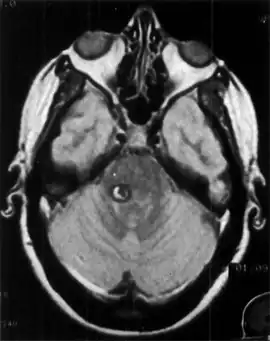

During a physical exam, a doctor can determine whether the tremor occurs primarily during action or at rest. The doctor will also check for tremor symmetry, any sensory loss, weakness or muscle atrophy, or decreased reflexes. A detailed family history may indicate if the tremor is inherited. Blood or urine tests can detect thyroid malfunction, other metabolic causes, and abnormal levels of certain chemicals that can cause tremor. These tests may also help to identify contributing causes, such as drug interaction, chronic alcoholism, or another condition or disease. Diagnostic imaging using CT or MRI imaging may help determine if the tremor is the result of a structural defect or degeneration of the brain.